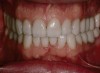

Figure 6  Preoperative retracted view of the dentition.

Figure 6